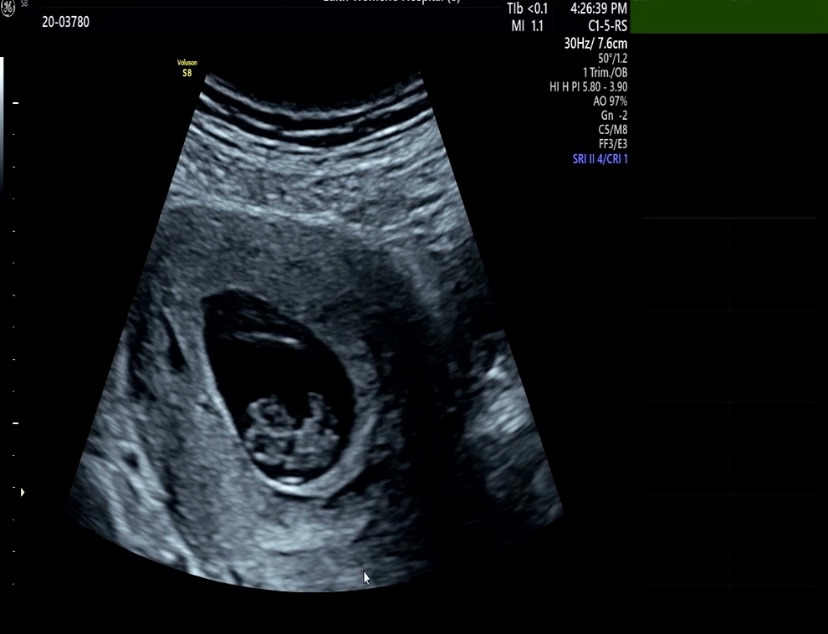

젤리곰을 봤다. 아직은 손가락 한마디 정도 되는 크기인데도, 사람 모습을 갖춰가는 게 너무 신기하다. 의사 선생님이 이제는 3~4주 뒤에 1차 기형아 검사를 할 때 보자고 하셨다. 1주일도 이렇게 긴데, 어떻게 그 시간을 기다릴지 벌써 걱정이다. 아내보고 건강한 산모라고 했다. 그래서 아기도 건강하게 잘 크고 있다고 한다. 만성 운동부족인 아내를 걱정하는 건 나뿐인가 보다. 그래도 전문가에게 그런 이야길 들으니 안심이 되고 힘이 난다.